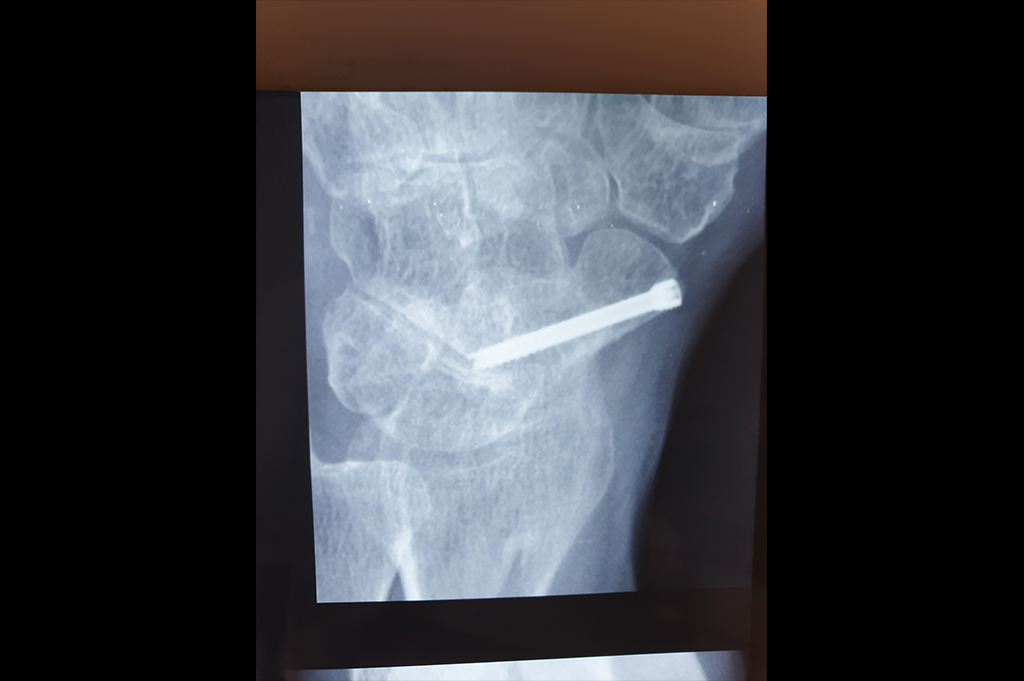

Scaphoid